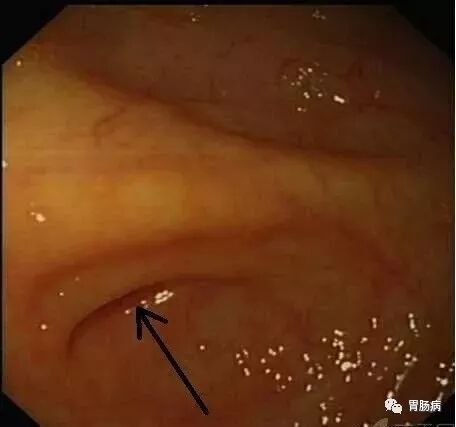

充分的肠道准备会有效减少ERAT操作时间,正常的阑尾开口部都被Gerlach’s瓣覆盖(如图,双箭头示Gerlach’s瓣);会造成插管困难,加上特制的锥形透明帽后插管就变得相对容易。

通过内镜前端的透明帽的帮助下,推开Gerlach’s瓣(黄箭头),并进行阑尾腔插管。